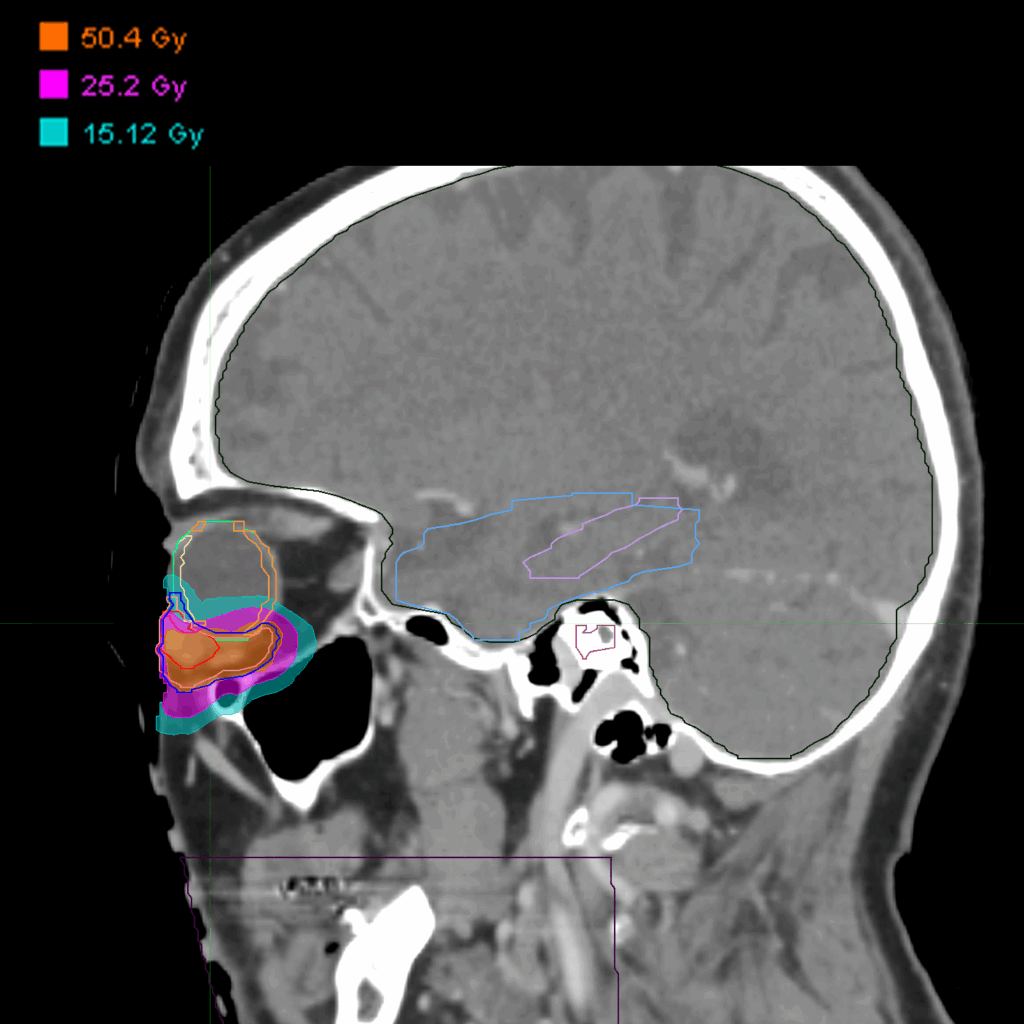

Treatment Plan Images

Fractionation

50.4 Gy in 14 fractions

Dose Distributions

- Prescription to the 76% isodose line

- Max. dose 66 Gy